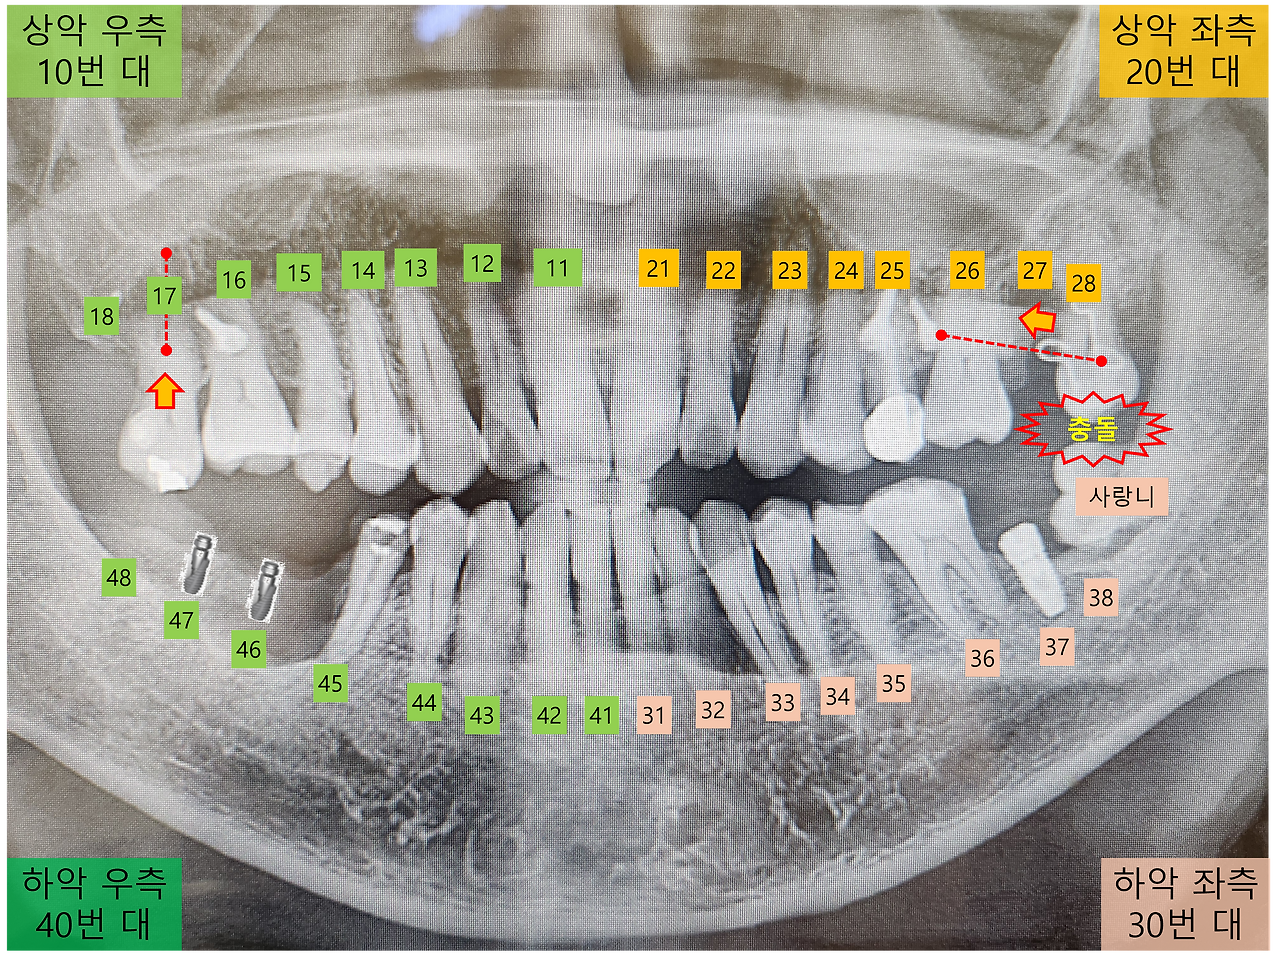

지난번 교정 장치 조정 후 일주일이 지나면서, 28번 치아가 다시 사랑니와 부딪치는 증상이 재발되었네요.

교정 중인 28번 치아의 불편함을 교정전문의에게 이야기를 했더니, 교합지를 사용하여 치아의 맞물림 상태를 확인합니다. 역시 예상한 데로 28번 치아와 사랑니 일부가 간섭이 된다며, 사랑니를 좀 갈아 내는 치료가 필요하다고 하네요.

[치아 충돌 위치]

간호사분이 조금씩 사랑니를 갈아 내면서, 치아의 맞물림 상태와 통증 여부를 세심하게 확인합니다.

너무 많이 갈아낼 경우 사랑니가 시큰거리는 증상이 있을 수 있답니다. 다행히도 부딪침이 사라지고 시큰거리지 않는 범위 내에서 치료는 완료되었습니다.

오른쪽 17번 치아는 내려온 치아를 잇몸 쪽으로 당겨 올리는 교정과 입 안쪽으로 당기는 교정을 동시에 진행 중이었습니다. 그런데 17번 치아가 안쪽으로 급격하게 당겨지는 경향이 있어, 바깥쪽은 고무줄 대신에 철사로 고정하여 더 이상 당겨지지 않도록 조정했던 것으로 알고 있습니다. 하지만 이번에는 치아 교정 장치의 안쪽과 바깥쪽 모두 고무줄로 연결하여 당기는 방식으로 변경이 되었네요.